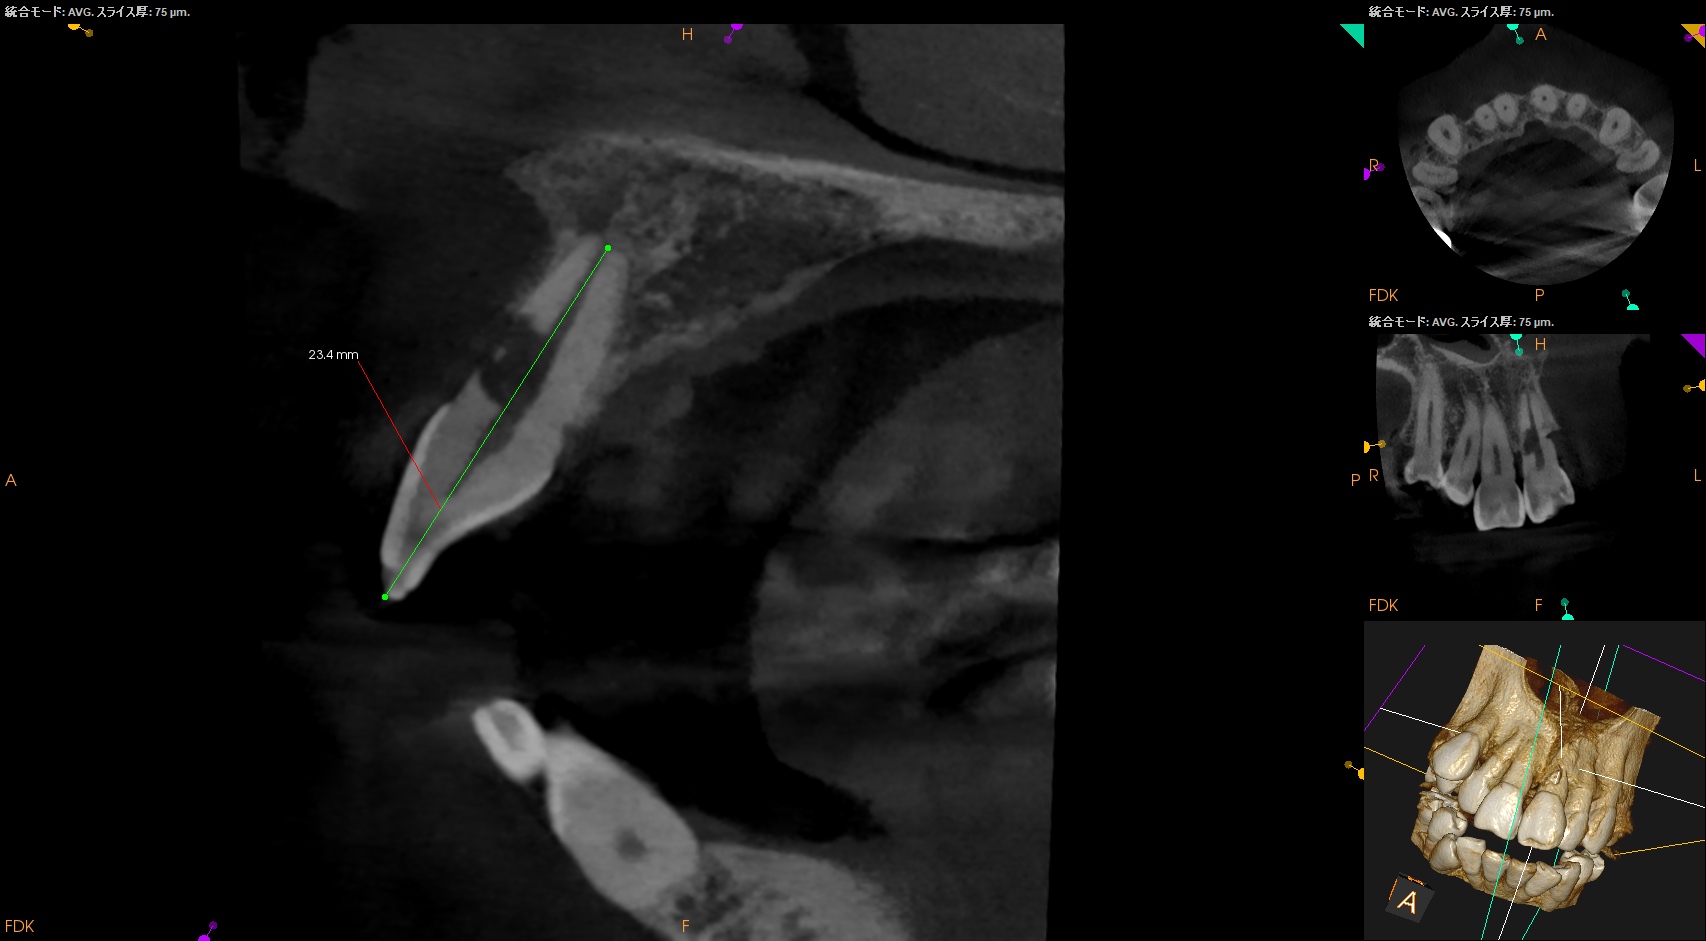

また、CBCTによればそのRIL(Radiographic Instrumentation Length)は23.4mmであるということがわかる。

そこから1mm引いた22.4mm程度が作業長だろう。

このことからもCBCTがなくては治療計画も立てられないということわかるだろう。